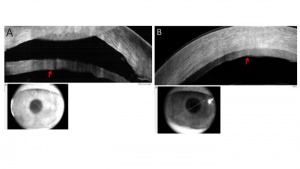

Conjunctival melanoma – subepithelial

AS-OCT images of melanomas typically show a hyperreflective, subepithelial lesion. The epithelium is normal or slightly thickened with variable hyperreflectivity of the basal epithelium, which suggests involvement of the epithelium with atypical melanocytes. This imaging can help to rule in or rule out a pigmented OSSN versus melanoma.[9][10] (Figure 4).

Conjunctival lymphoma – subepithelial

On AS-OCT, conjunctival lymphoma is characterized by a normal layer of epithelium overlying homogenous, dark, hyporeflective subepithelial lesions with smooth, discrete borders. The lesions can often contain monomorphic, stippled, dot like infiltrates that correspond to the infiltration of monoclonal lymphocytes.[9] (Figure 5).